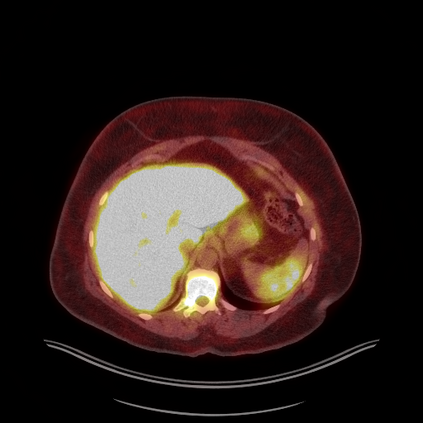

Medical images play a crucial role in assisting diagnosis, remote consultation, and academic research. However, during the transmission and sharing process, they face serious risks of copyright ownership and content tampering. Therefore, protecting medical images is of great importance. As an effective means of image copyright protection, zero-watermarking technology focuses on constructing watermarks without modifying the original carrier by extracting its stable features, which provides an ideal approach for protecting medical images. This paper aims to propose a fragile zero-watermarking model based on dual quaternion matrix decomposition, which utilizes the operational relationship between the standard part and the dual part of dual quaternions to correlate the original carrier image with the watermark image, and generates zero-watermarking information based on the characteristics of dual quaternion matrix decomposition, ultimately achieving copyright protection and content tampering detection for medical images.